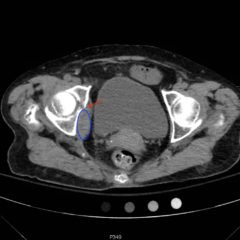

An elderly female with no history of prior abdominal surgeries presented to the emergency department (ED) with acute onset of abdominal pain and distention.  Upon arrival, she began having large volume bilious emesis. While waiting for a computed tomography (CT) scan of her abdomen and pelvis, a point of care ultrasound (POCUS) was performed which showed evidence of a small bowel obstruction (SBO). The patient had a nasogastric tube placed that put out over two liters of bilious contents. A subsequent CT scan confirmed the diagnosis of SBO from a left inguinal hernia and the patient was admitted to the surgical service.

The POCUS utilizing the low frequency curvilinear probe demonstrates fluid-filled, dilated bowel loops greater than 2.5cm with to-and-fro peristalsis, and thickened bowel walls greater than 3mm, concerning for SBO.

Gastrointestinal obstruction is a common diagnosis in the ED, accounting for approximately 15% of all ED visits for acute abdominal pain.1 SBO accounts for approximately 80% of all obstructions.2 In the diagnosis of SBO, studies show that abdominal x-rays have a sensitivity of 66-77% and specificity of 50-57%,3 CT scans have a sensitivity of 92% and specificity of 93%,4 and ultrasound has a sensitivity of 88% and specificity of 96%.5

While CT scan remains a widely accepted modality for diagnosing SBO, ultrasound is more cost effective, well tolerated, does not involve ionizing radiation, and can be done in a timely manner at the patient’s bedside. Ultrasound can also identify transition points as well as distinguish between functional and mechanical obstruction.6 In addition to SBO, ultrasound can be used to diagnose external hernias, intussusception, tumors, superior mesenteric artery (SMA) syndrome, foreign bodies, bezoars, and ascariasis.7